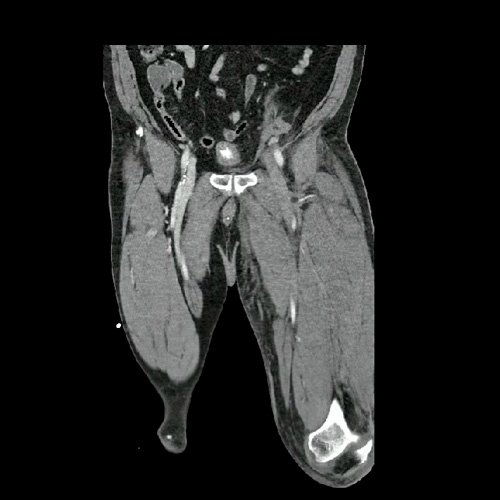

• AngioTAC de miembros inferiores (Día 2): Ateromatosis parietal calcificada parcheada en todo el territorio aorto-ilíaco-femoral bilateral. LADO DERECHO: Arteria ilíaca interna: de calibre y trayecto conservado, permeable. Arterias ilíaca externa y femoral común: de calibre y trayecto conservados, permeables. Arterias circunfleja ilíaca superficial y epigástrica superficial: de calibre y trayecto conservados, permeables. Arteria femoral superficial: de calibre y trayecto conservado, permeable. Arteria femoral profunda: de calibre y trayecto conservado, permeable. Arterias circunflejas femoral medial y lateral: de calibre y trayecto conservados, permeables. Arteria poplítea: de calibre y trayecto conservado, permeable. Arteria tibial anterior: de calibre y trayecto conservado, permeable. Arteria tibial posterior: de calibre y trayecto conservado, permeable. Vena ilíaca primitiva: 13 mm, vena ilíaca externa 11 mm, vena ilíaca interna 7 mm. LADO IZQUIERDO: En esta ocasión, en fase angiográfica se observa de calibre y opacificación conservada de las arterias femoral superficial y profunda, poplítea y de sus ramas musculares en muslo y pierna. En fase venosa se evidencia un defecto de relleno endoluminal de la vena primitiva izquierda que impresiona extenderse actualmente a la vena iliaca externa, a la vena femoral superficial y poplítea, hasta nivel del hueco homonimo, las cuales se visualizan aumentadas de calibre con respecto a sus contralaterales, en relación a trombosis venosa profunda. Se sugiere cotejar con ecodoppler de miembros inferiores. No se identifica compromiso de la porción visualizada de la vena cava inferior ni del sistema venoso ilíaco contralateral. Se visualiza dispositivo vascular en VCI (filtro VCI), infrayacente a las venas renales. Presenta aumento del diámetro del muslo izquierdo con respecto a su contralateral, asociado a edema de los tejidos blandos superficiales. Reticulación de la grasa de la región inguinal a predominio izquierdo con algunas burbujas aéreas. Se observa inmediatamente infrayacente a los antes mencionado, un área hiperdensa que realza en fase venosa, con centro hipodenso, que mide 2.2 cm x 1.4 cm, ya visualizado en tomografía previa. Cambios artrodegenerativos coxo-femorales y tricompartimentales en la rodilla. Signos de entesopatía cuadricipital distal. No se observan alteraciones a nivel del fémur ni de las porciones visualizadas de la tibia y el peroné. Arteria ilíaca interna: de calibre y trayecto conservado, permeable. Arterias ilíaca externa y femoral común: de calibre y trayecto conservados, permeables. Arterias circunfleja ilíaca superficial y epigástrica superficial: de calibre y trayecto conservados, permeables. Arteria femoral superficial: de calibre y trayecto conservado, permeable. Arteria femoral profunda: de calibre y trayecto conservado, permeable. Arterias circunflejas femoral medial y lateral: de calibre y trayecto conservados, permeables. Arteria poplítea, tibial anterior y tibial posterior: de calibre disminuido con respecto a su contralateral, permeables. Vena ilíaca primitiva: 14 mm, vena ilíaca externa 17 mm, vena ilíaca interna 9 mm. Calcificaciones en conducto inguinal bilateral. Hidrocele bilateral.

Angio TAC de miembros inferiores (Día 2)